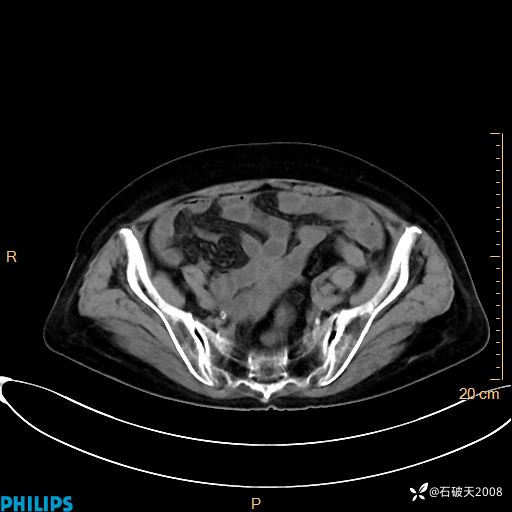

平扫